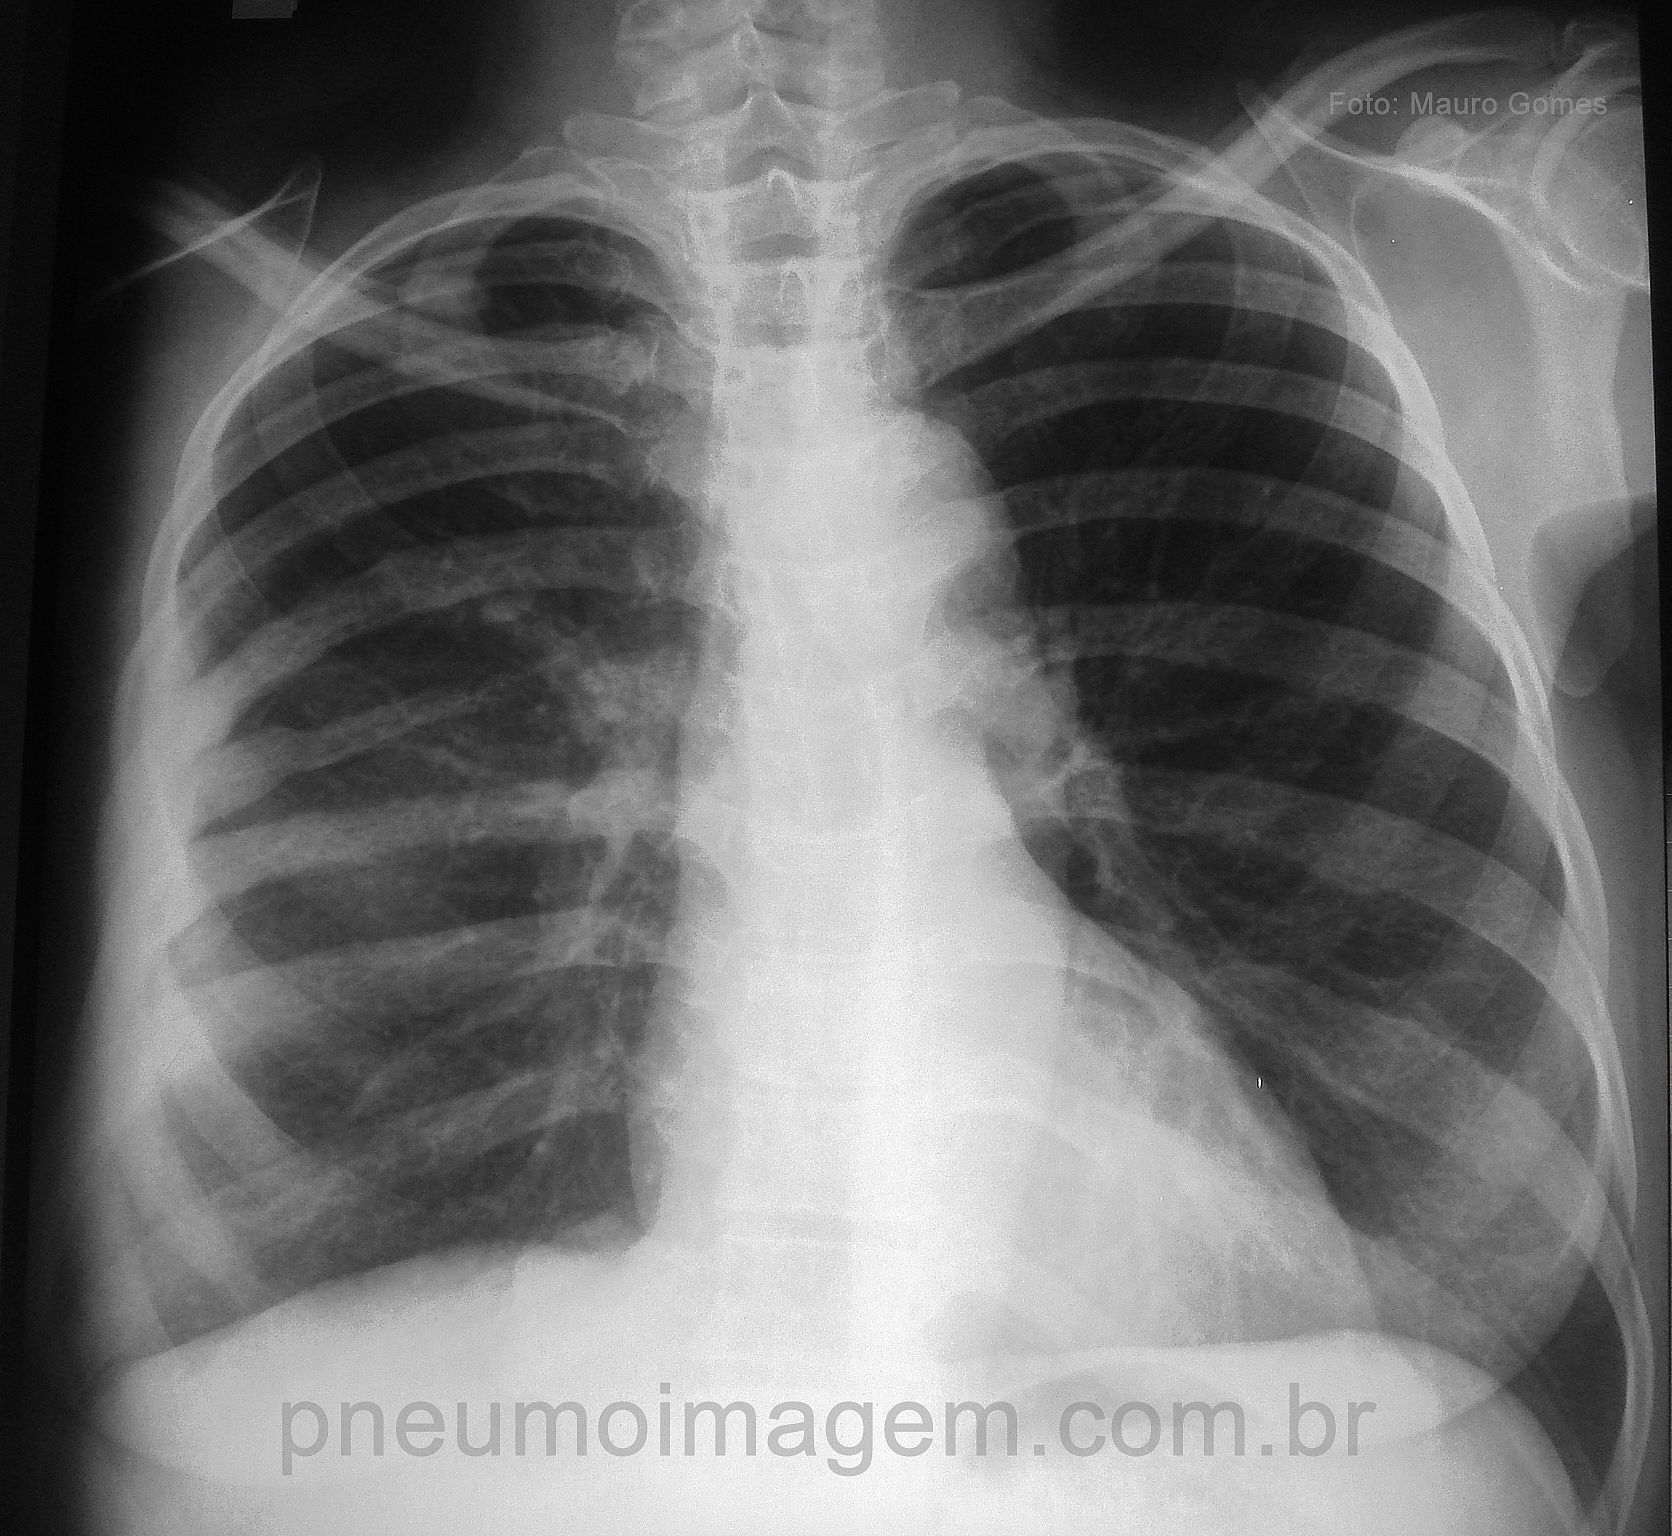

CASO CLÍNICO #29Mulher com câncer de mama foi submetida a tratamento por radioterapia e apresenta dor torácica. Qual o diagnóstico mais provável? Deixe os seus comentários abaixo.

Woman with breast cancer underwent treatment by radiotherapy and presents chest pain. What is the most likely diagnosis? Give your comments below.

FRATURA DE COSTELAS DIREITAS POR METÁSTASES.

Fratura por metástase em costelas direitas.

Osteoporose (devido RxT) em região de costela, podendo ter ocasionado possível fratura da mesma.